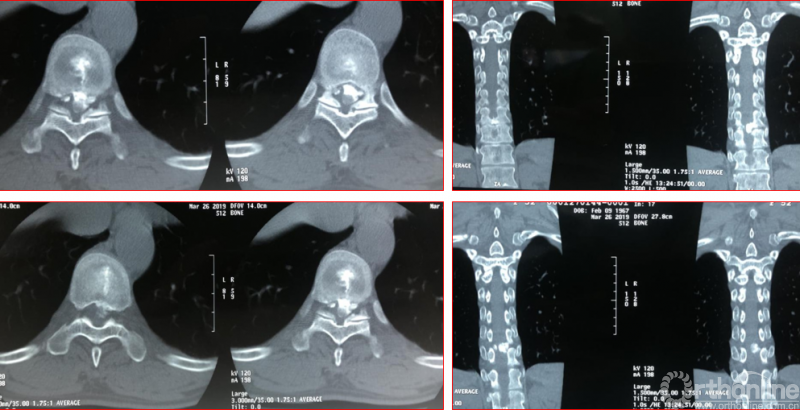

术中资料

点击以上图片,查看术中视频(超链接:http://res.orthonline.com.cn/video/case5---20.mp4)

点击以上图片,查看术中视频(超链接:http://res.orthonline.com.cn/video/case5---30.mp4)

术后影像学资料